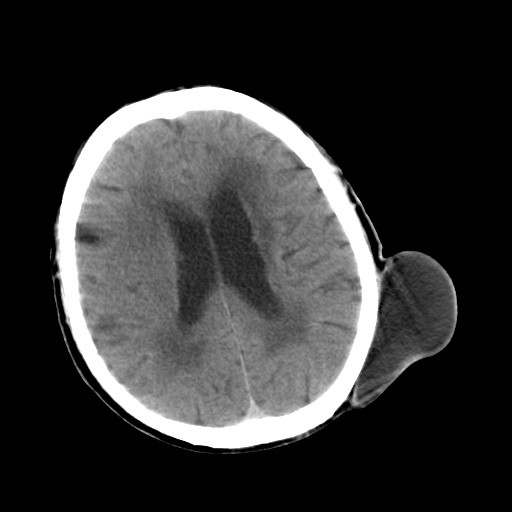

标题: CT25147:男,62岁,右侧肢体活动障碍不灵活三天。 [打印本页]

男,62岁,右侧肢体活动障碍不灵活三天,左侧头皮肿物十余年(ct值8hu)。

多发腔梗!皮下脂肪瘤!

1)多发性腔隙性脑梗塞。2)脑白质病。3)脑萎缩。4)左侧枕顶部头皮下皮样囊肿,不排除脂肪瘤。

1)多发性腔隙性脑梗塞。2)脑白质病。3)脑萎缩。4)左侧枕顶部头皮下皮样囊肿或表皮样囊肿。